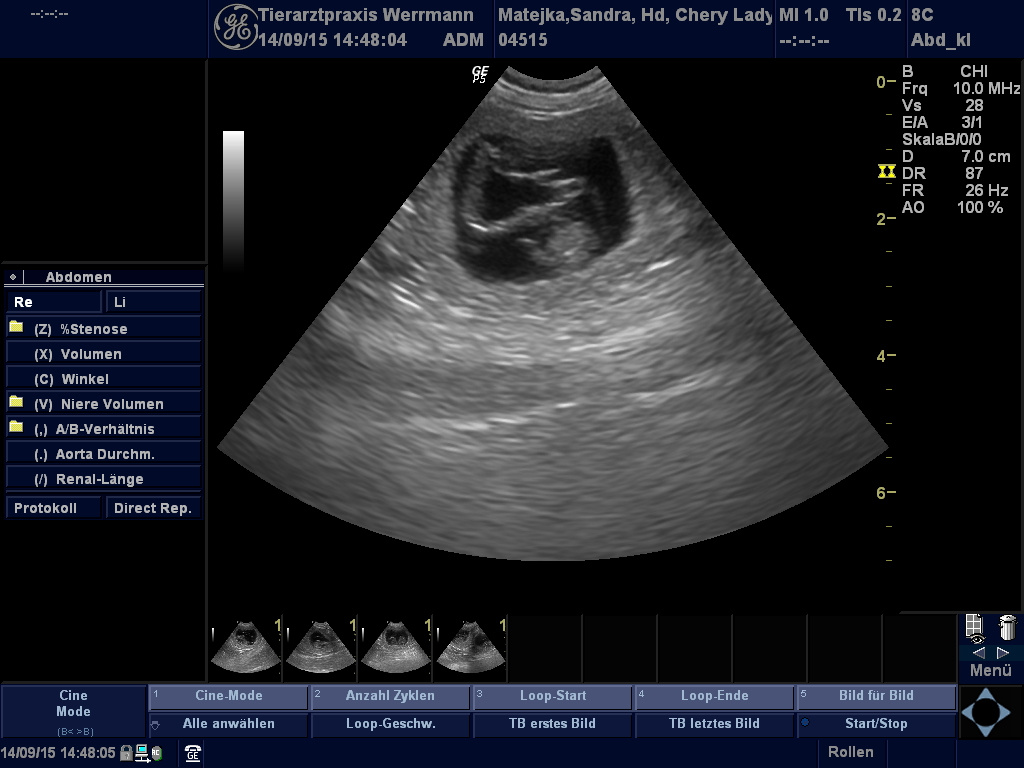

Ultraschallbilder